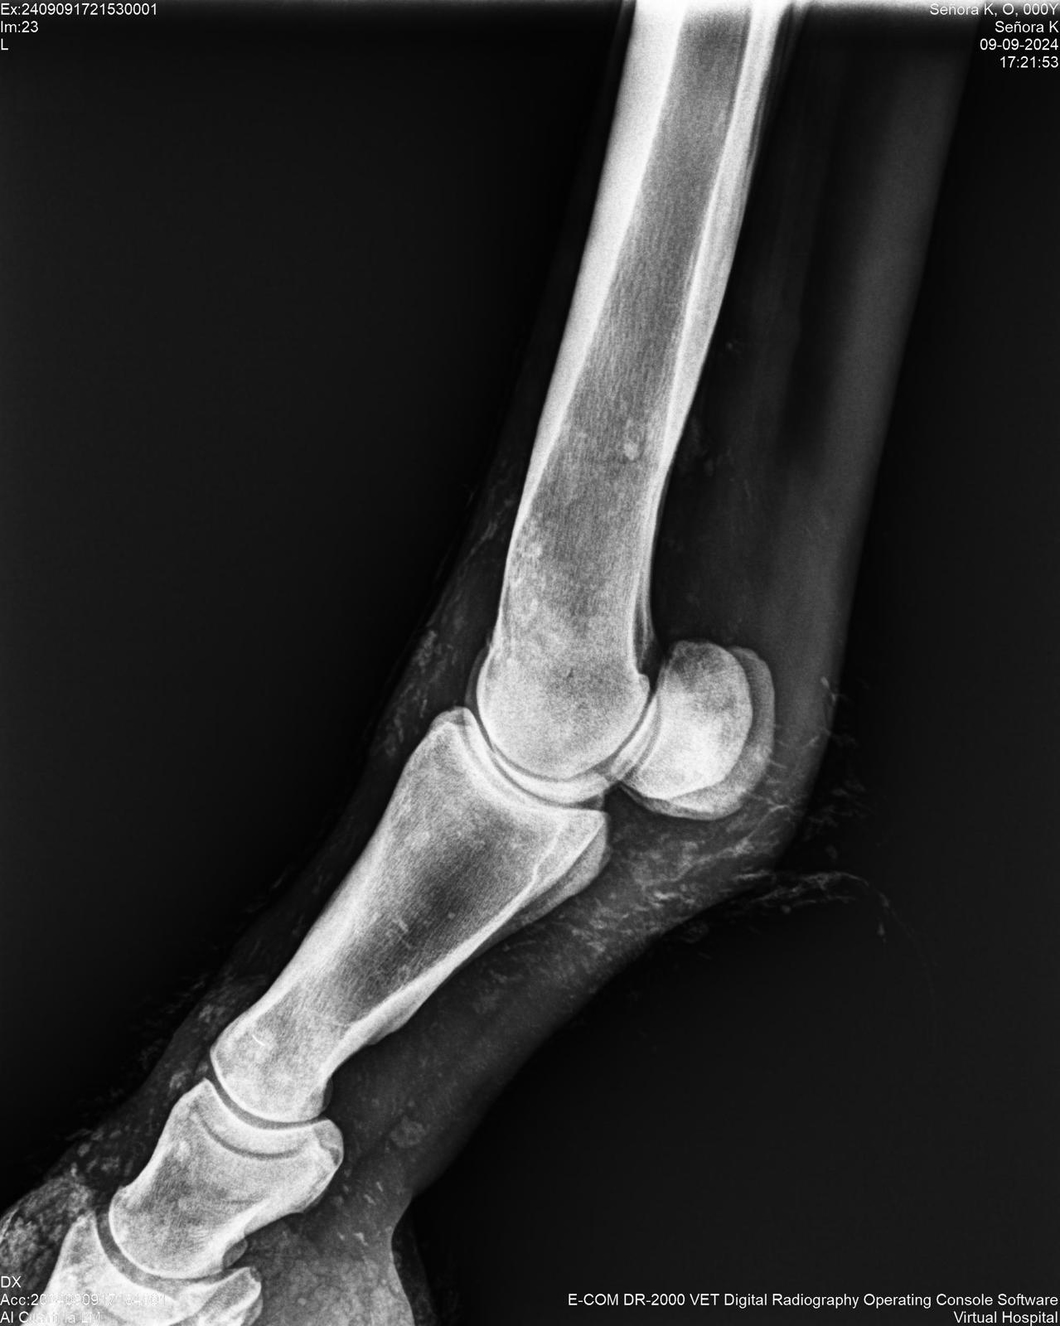

LOTE 44, SEÑORA K

Identificador: #291147-

Generacion 2022